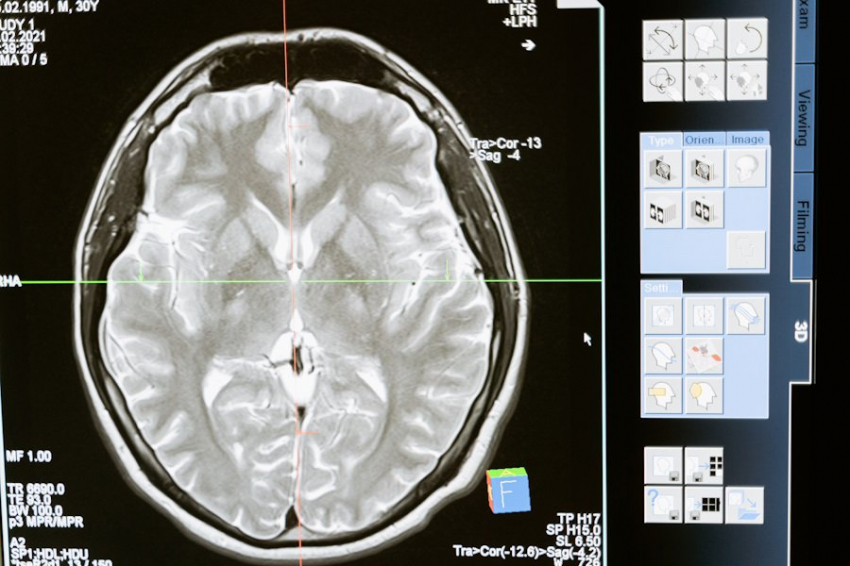

Исследователи из Университета Юты создали уникальное ультразвуковое устройство, которое устанавливается на голове и воздействует на глубокие структуры мозга. Устройство под названием «Диадема» уже прошло два успешных испытания на людях, продемонстрировав свою эффективность в лечении хронической боли и депрессии, сообщает PAIN.

Первое испытание показало, что направленные звуковые волны могут значительно уменьшить симптомы боли. В исследовании участвовали 20 пациентов с хронической болью, которые получали 40-минутные сеансы активной или фиктивной стимуляции. Результаты показали, что после активной стимуляции боль уменьшилась в среднем на 60% сразу после процедуры и продолжала снижаться на 43% и 33% в течение недели. Для сравнения, фиктивная стимуляция дала гораздо менее значительный эффект.

Во втором испытании была изучена эффективность устройства в лечении депрессии. Уже после одного сеанса ультразвуковой стимуляции у пациентов наблюдалось заметное улучшение симптомов. Этот неинвазивный подход может стать альтернативой более сложным и инвазивным методам, таким как цингулотомия и глубокая мозговая стимуляция, которые требуют хирургического вмешательства.

Устройство «Диадема» хорошо переносится пациентами, побочные эффекты минимальны и проходят в течение 24 часов. Эти данные свидетельствуют о том, что ультразвуковая стимуляция передней поясной извилины может стать новым, эффективным и безопасным методом лечения хронической боли и депрессии.